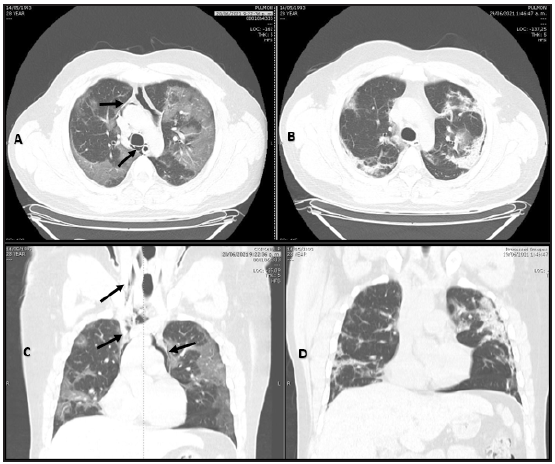

Figure 2 Patient 2. A and C: Simple chest CT. Axial and coronal planes. Air in the mediastinum extending towards the upper chest and lower neck. Black arrows. B and D: no air is seen nine days later.